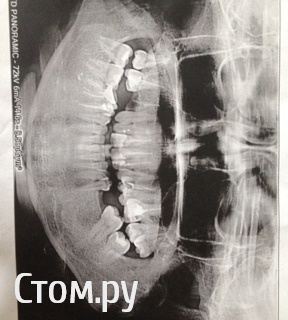

Ирина17 Опубликовано 13 августа, 2014 Поделиться Опубликовано 13 августа, 2014 (изменено) Добрый день! Ситуация следующая.... Ходила к разным врачам, одни утверждают, что нужно ставить импланты, другие категорически против имплантов, предлагают исправить прикус, 5 зубов с пломбами заменить коронками и мост на место удаленных зубов..кого слушать,непонятно! Буду благодарна за консультацию! Мне 28 лет. с 14-15 лет смыкаю зубы, и так мне удобно ходить ( привыкла) ( фото номер 1 ) , а вообще у меня глубоких прикус. Панорамный снимок челюсти могу скинуть на эл. почту, тк здесь не загружается Изменено 13 августа, 2014 пользователем Ирина17 Ссылка на комментарий